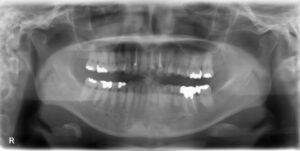

下顎大臼歯1本欠損症例

BEFORE AFTER 53歳女性/下1本欠損/インプラント埋込手術 【治療内容】 歯根の先で炎症が広がり、抜歯となっ…